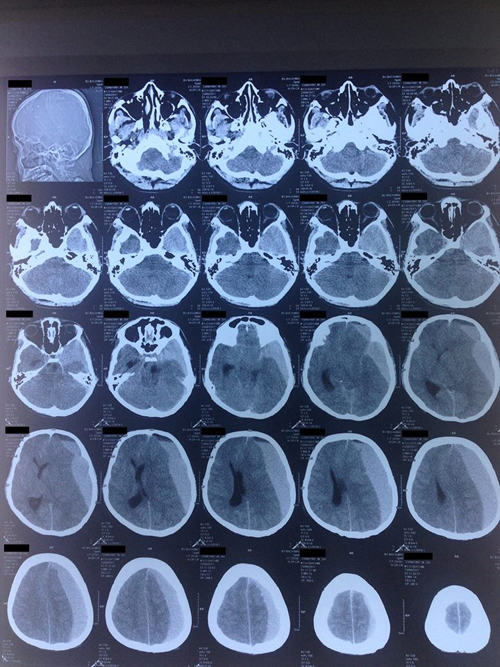

Một điều thật sự buồn đối với các bác sĩ, với cả gia đình và bạn bè của bệnh nhân rằng kết quả phim chụp cắt lớp vi tính sọ não cho thấy hình ảnh tụ máu dưới màng cứng bán cấp rất lớn ở bán cầu đại não trái. Máu tụ dưới màng cứng đã gây một hiệu ứng khối lên toàn bộ não và gây phù não rất mạnh làm tụt kẹt các thùy não. Chính điều này là nguyên nhân khiến bệnh nhân bị ngừng tuần hoàn.

Hình ảnh chảy máu dưới màng cứng bán cấp bên bán cầu não trái trên phim CT sọ não của bệnh nhân trẻ tuổi. |